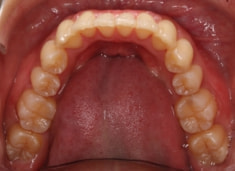

症例紹介

左上3番埋伏歯

治療法:フルパッシブブラケット:T21

治療後(2年後)